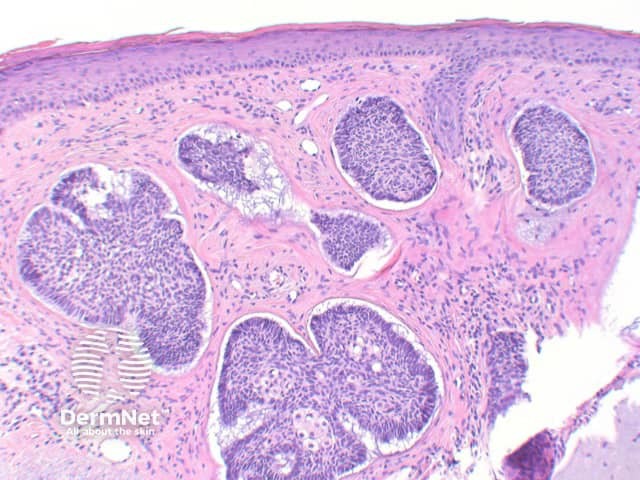

The key feature of basal cell carcinoma at low power magnification is of a basaloid epithelial tumour arising from the epidermis (figure 1). The basaloid epithelium typically forms a palisade with a cleft forming from the adjacent tumour stroma (figure 2). Centrally the nuclei become crowded with scattered mitotic figures and necrotic bodies evident (figure 3). A useful distinguishing feature from other basaloid cutaneous tumours is the presence of a mucinous stroma (figure 4). Some tumours may also show foci of regression, seen as areas of eosinophilic stroma with lack of basaloid nests.

Figure 4